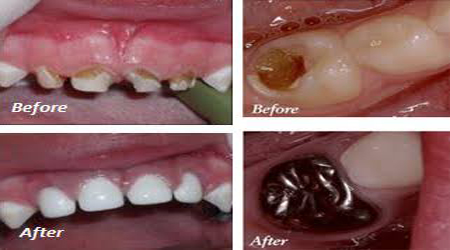

Pulpectomy (RCT) 3500-5500 50-75

Stainless Steel Crown 3500-5000 50-70

Esthetic Crown (Tooth Like) 4000-6000 55-85